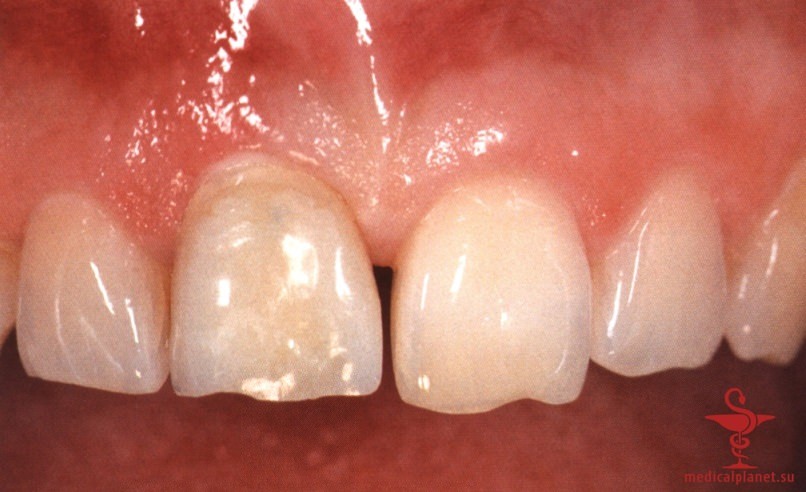

В качестве альтернативы можно провести пересадку субэпителиального соединительнотканного трансплантата (СТТ) для перекрывания лунки, избегая коронального смещения лоскута. Однако следует помнить, что выполнение нескольких хирургических манипуляций одновременно повышает риск нарушения кровоснабжения, от которого во многом зависит качество заживления. При этом часть СТТ остается открытой и заживает вторичным натяжением в течение относительно длительного периода.

Более того, происходит потеря объема трансплантата, а результат редко можно признать оптимальным, особенно в области десневых сосочков (рис. 2), поэтому в настоящее время такой протокол не рекомендуется.